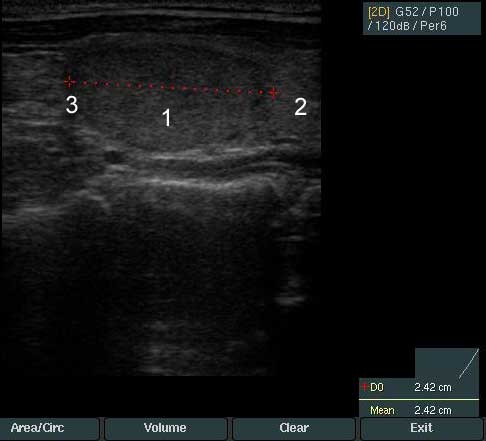

1. Узел щитовидной железы - Размер узла 1,9 на 1,2 на 2,4 см.

Узел по структуре изоэхогенный с четкими контурами и ободком Halo. По данным допплеровского исследования кровоток в узел смешанного типа - перинодулярный и интранодулярный.

В связи с тем, что размер узла более 10 мм, пациентке предложена тонкоигольная аспирационная биопсия.

Под контролем УЗИ выполнена биопсия узла щитовидной железы.